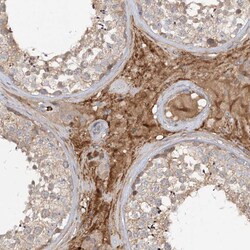

Invitrogen™ FGF19 Polyclonal Antibody

Brand: Invitrogen™ PA5111069

| Immunohistochemistry (Paraffin) | |